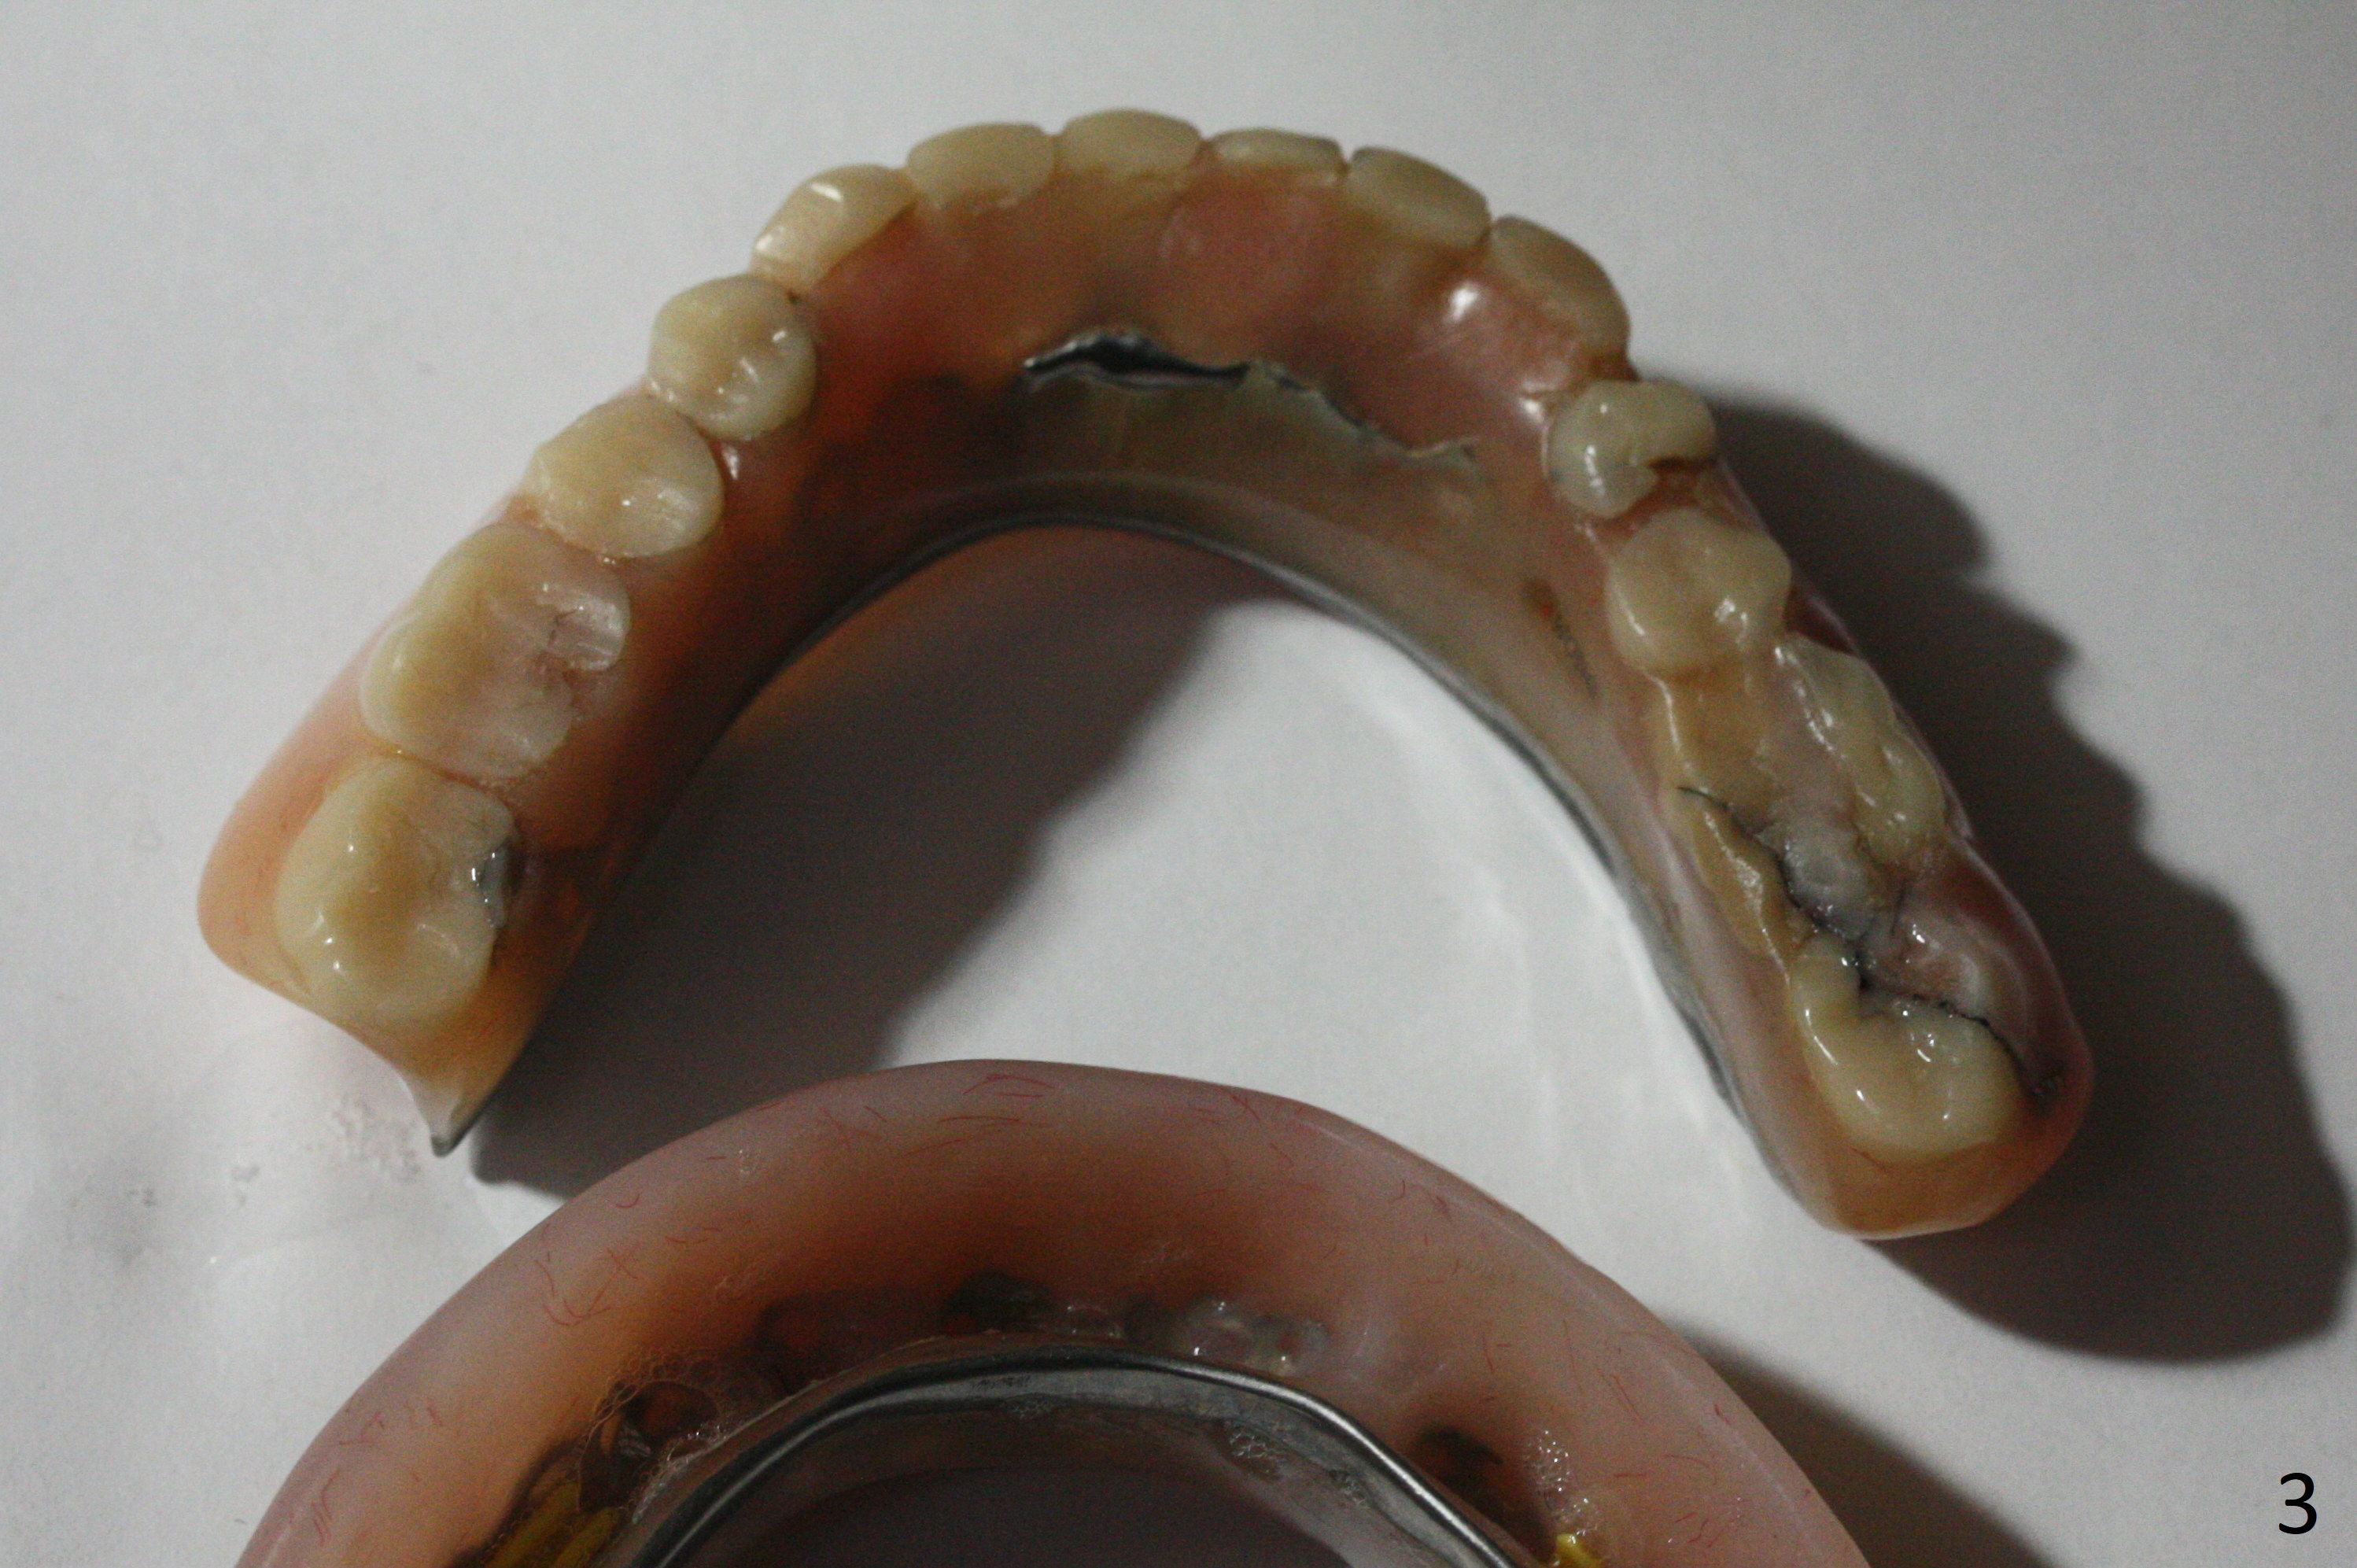

A 77-year-old man presents to clinic with chief complaint of loose lower denture, which is ~ 15 years old (Fig.1-6). The implants were placed ~ 30 years ago. There is wear and crack of the denture teeth (Fig.3). When the denture is remade, make metal occlusal surface at the premolar and molar region. An extra existing denture will be sent to lab for reference. What is the best method to take the lower impression? Block metal framework undercuts? Alginate or PVS?